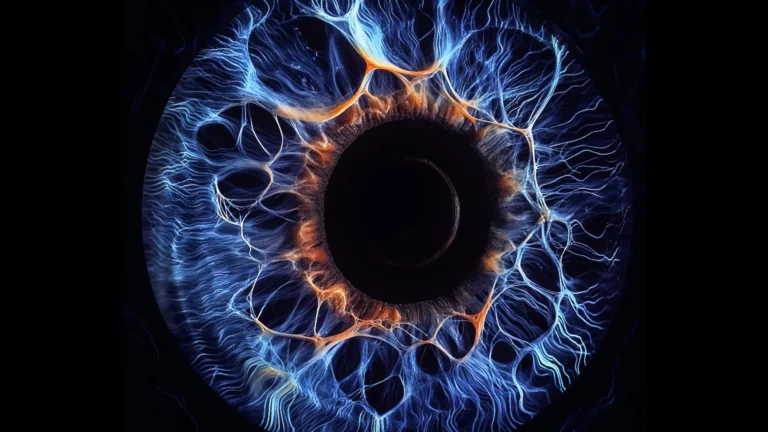

To unravel the precise molecular mechanisms by which D-Cys exerts its detrimental effects on cancer cells, the researchers collaborated with Professor Roland Lill and his team at the University of Marburg. Their joint efforts uncovered that D-Cys directly interferes with an indispensable enzyme named NFS1. This enzyme resides within the mitochondria, often dubbed the "powerhouses" of the cell due to their central role in energy production. NFS1 is vital for the synthesis of iron-sulfur clusters, intricate small structures that are absolutely essential cofactors for a multitude of fundamental cellular processes. These processes include cellular respiration, the intricate biochemical pathways that generate ATP (the cell’s primary energy currency); the production of DNA and RNA, which are the blueprints and messengers of genetic information; and the maintenance of genomic integrity, ensuring accurate replication and repair of the cell’s genetic material.